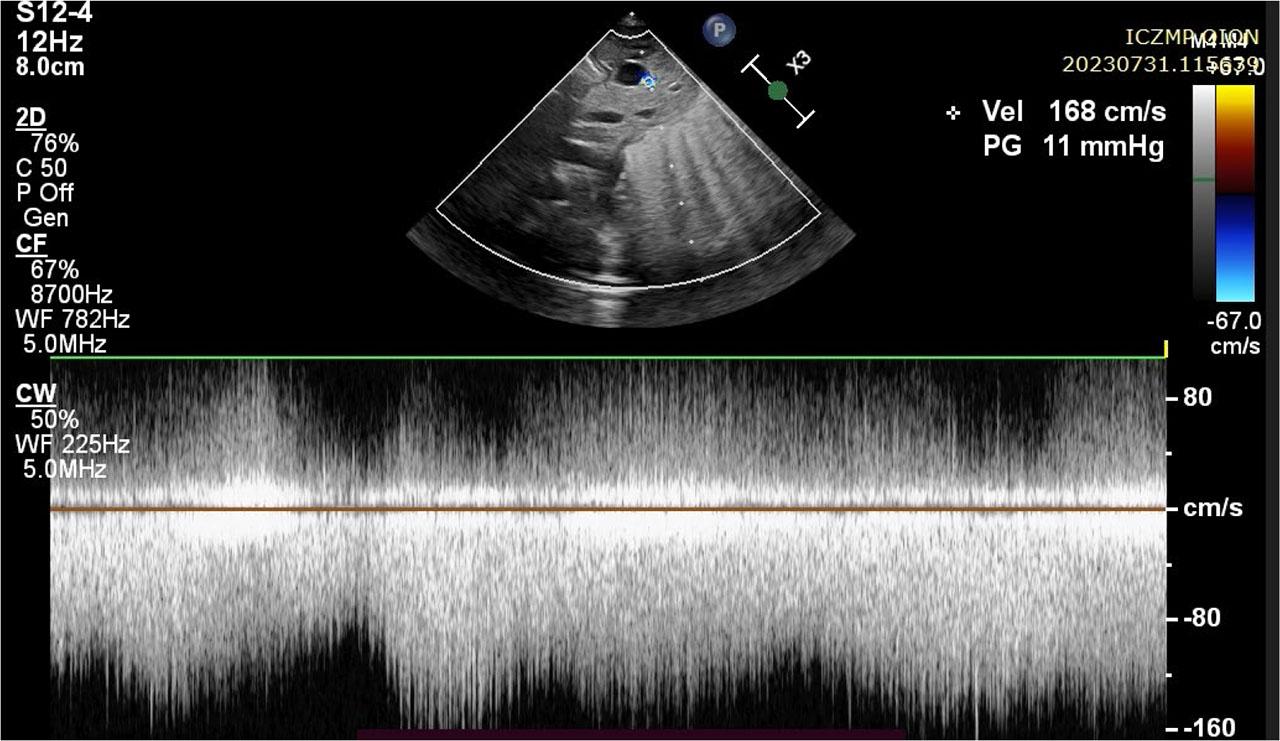

| PA [mm] | 4.5 | 7.2 | 7.2 |